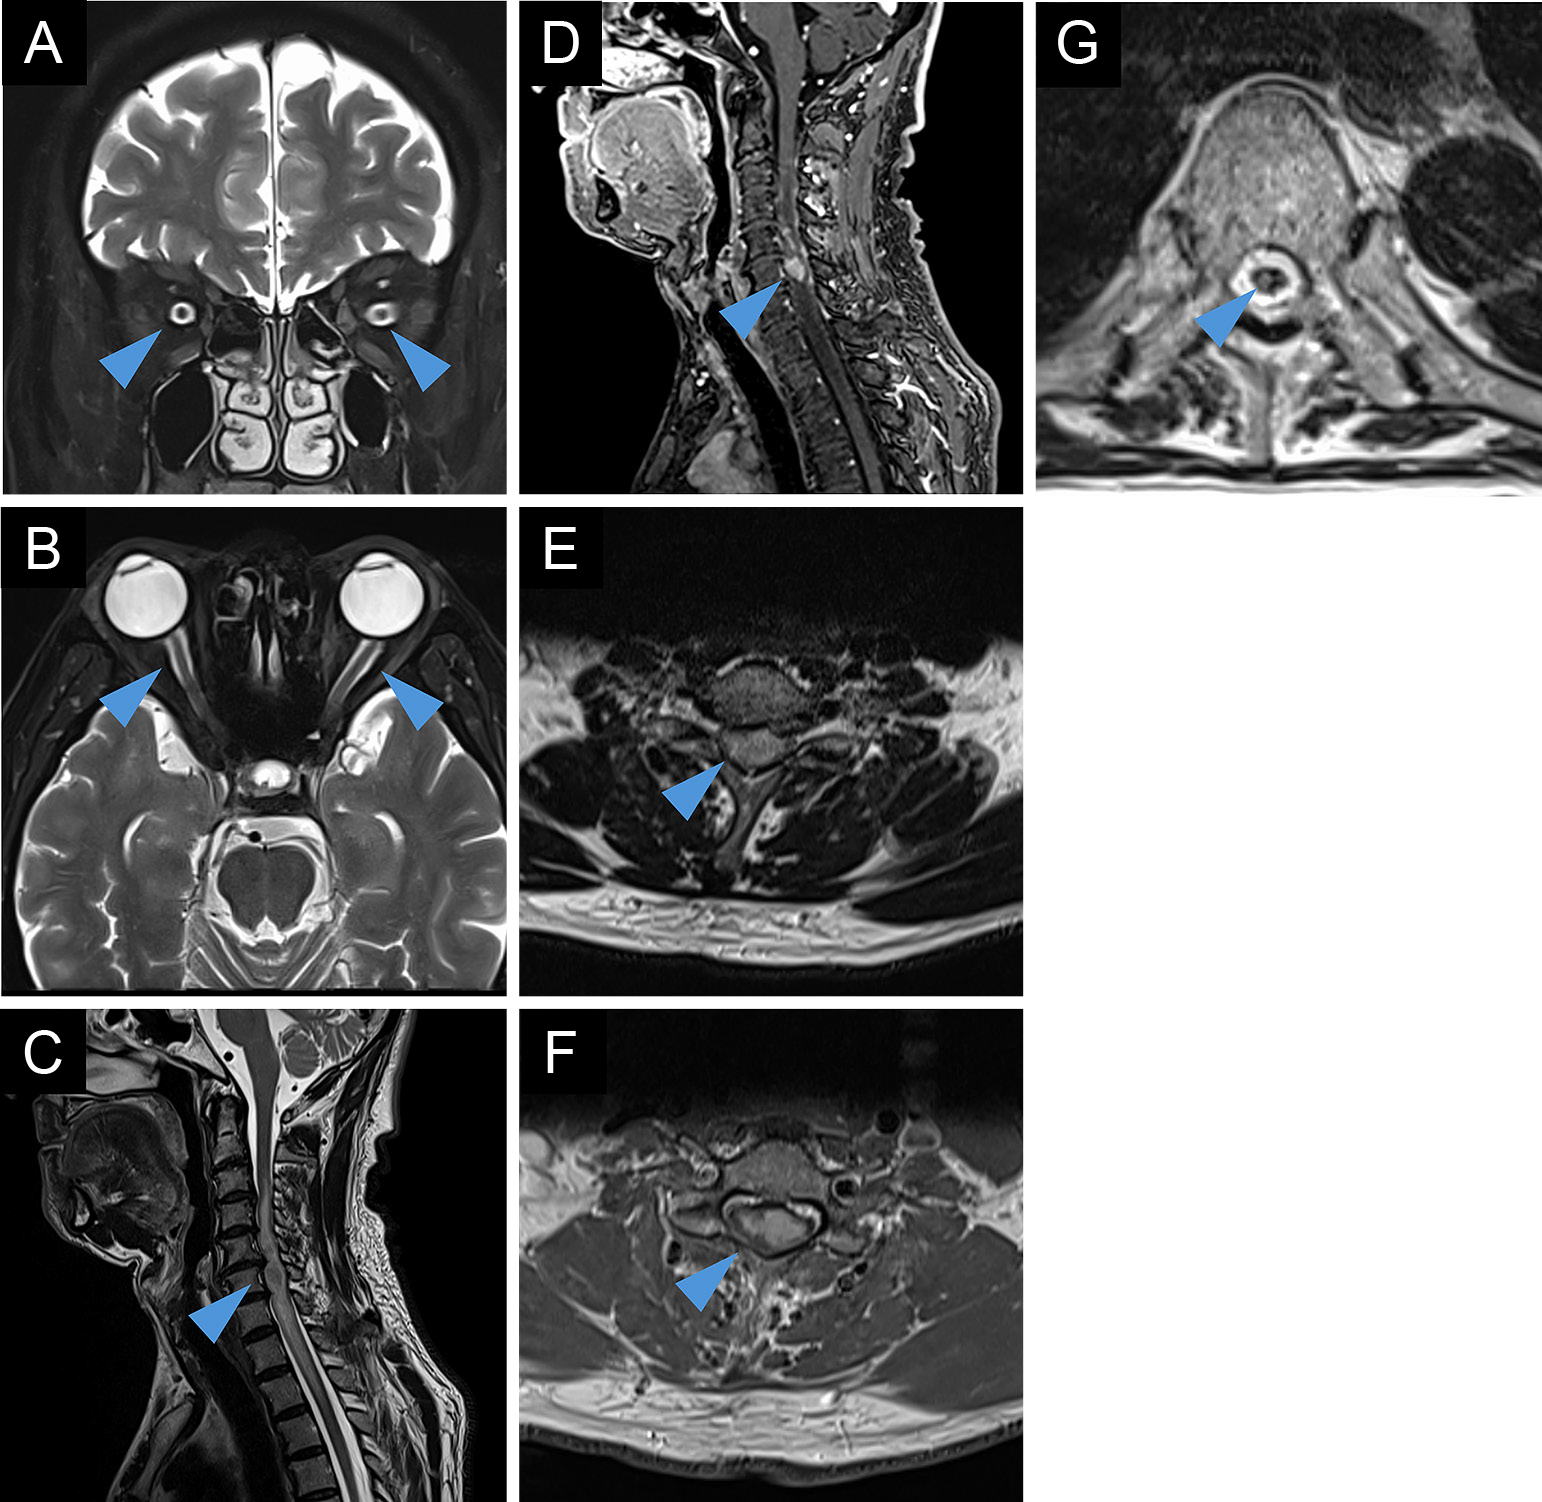

A case of myelin oligodendrocyte glycoprotein antibody-associated disease presenting with radiculopathies

Sunao Takahashi, Takashi Irioka, Ryo Iwase, Susumu Igarashi, Toshiyuki Takahashi